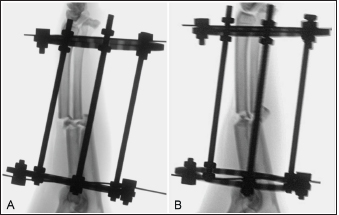

Fig. 2. Fluoroscopic images of a limb assigned to the cranial plating group obtained after application of the circular construct. The Kirschner wires were placed from medial to lateral. Note that the distal fracture segment is medially displaced after the radius and ulna had been distracted out to length (A). Manual pressure was applied to the medial aspect of the distal radial segment to translate the segment laterally along the implanted Kirschner wire to improve frontal plane alignment (B).

The total procedure time as well as incremental times for the subcategories of fixator placement, reduction, radial approach, and plate application did not differ between the cranial and medial plating groups (Table 1). Placement of the proximal Kirschner wire was more cumbersome than distal wire placement in both plating groups. Proximal cranial-to-caudal Kirschner wire placement was also more challenging than medial-to-lateral wire placement. Wire obliquity had to be addressed in four limbs in the cranial plating group and five limbs in the medial plating group. Obliquity was addressed by placing flat washers on one or both of the fixation bolts securing the Kirschner wire (n=1 limb in each plating group), attaching the fixation wire on opposite surfaces of the ring (n=1 and 2 in the cranial and medial plating group, respectively), or removing and replacing the wire (n=4 and 3 in the cranial and medial plating group, respectively). Lateral translation of the distal fracture segment along the Kirschner wire was performed to improve frontal plane alignment prior to plating in three limbs in the cranial plating group (Fig. 2). Caudal translation of the distal fracture segment along the Kirschner wire was performed to improve sagittal plane alignment prior to plating in two limbs in the medial plating group (Fig. 3). Obtaining sufficient exposure of the proximal radius to allow for plating required substantial tissue dissection, particularly in larger cadavers in both plating groups. The distal ring interfered with establishing a distal-to-proximal epiperiosteal tunnel in one limb in the cranial plating group, necessitating proximal-to-distal development. Plate orientation was more craniomedial than medial in six limbs in the medial plating group. Bone-holding forceps were used to improve reduction and alignment and to maintain appropriate plate position on the radius during plating in five limbs in the cranial plating group and six limbs in the medial plating group. Alignment was also similarly improved using bone holding forceps following initial plate placement by loosening then retightening or removing and replacing screws in four limbs in both plating groups (Fig. 4). The proximal or distal ring interfered with inserting the locking drill guide into the plate in three limbs in both plating groups. The fixator was removed in these limbs to allow placement of the final proximal or distal screw. Total and incremental procedure subcategory Likert scores assessing ease of performance did not differ between plating groups (Table 2). The number of fluoroscopic images (mean ± SEM: 8.7 ± 0.9 and 9.0 ± 0.8 for cranial and medial plating groups, respectively) obtained during the procedure did not differ between plating groups (p =0.77).